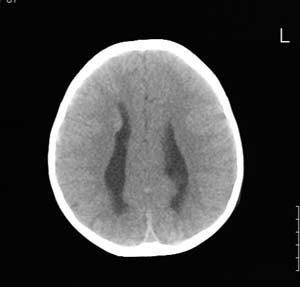

以下是引用lixi在2006-12-5 21:06:00的发言:[br]1、dandy-walker变异。2、胼胝体发育不良。

以下是引用zhuoshandiao在2006-12-5 21:41:00的发言:[br]胼胝体发育不良应该是肯定的。另外考虑dand-walker畸形。

以下是引用卜一在2006-12-5 22:30:00的发言:[br]支持考虑:1、dandy-walker变异。2、胼胝体发育不良